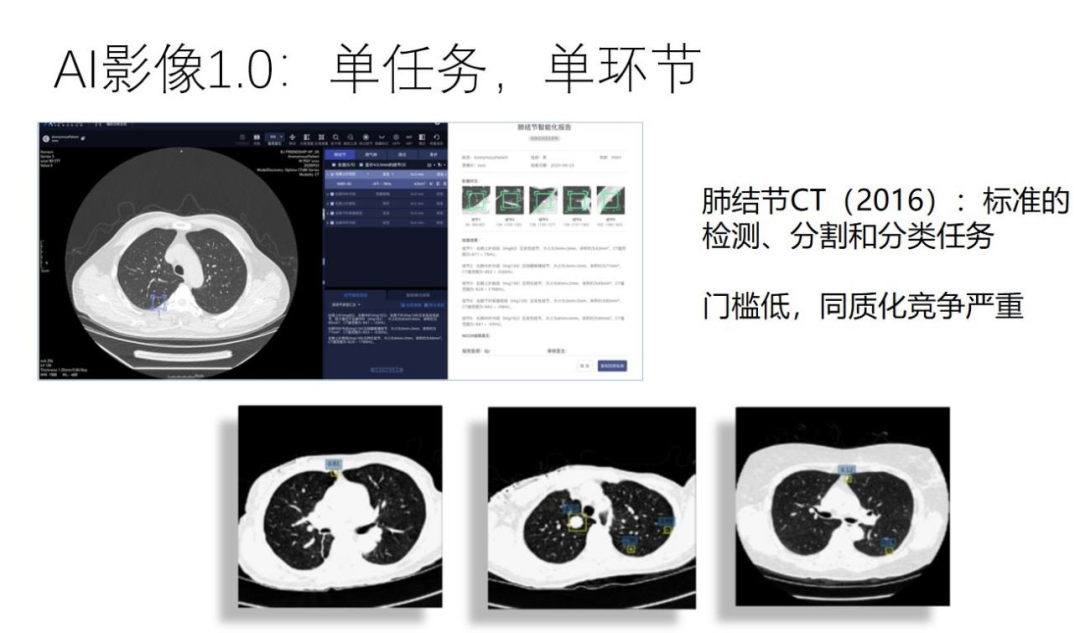

在 1.0 阶段,大家都扎堆做肺结节影像,这个任务相对来说比较简单,在 CT 图像上进行结节的检测、分割以及良恶性的分类,只需要有一些数据和基本的深度学习、图像的算法经验就可以做起来,门槛低,同质化竞争严重。同时产品的市场竞争力和盈利能力也是比较低的。

2016 年,很多大公司、创业公司开始入场 AI + 医疗领域,也存在一些同质化的竞争,例如当时做肺结节影像的特别多,投资也非常狂热。整个医疗行业包括医院和医生刚开始接触 AI,持着将信将疑的态度开始尝试。